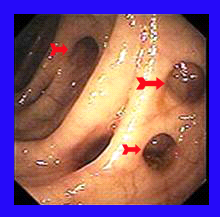

- סיגמואידוסקופיה (תצפית המעי הסיגמואידי): מראה את פתחי הסעיפים או היצרויות של הכרכשת.